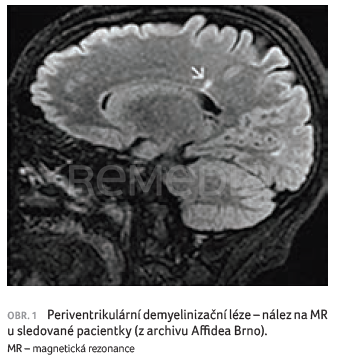

Roztroušená skleróza (RS) jako chronické onemocnění vyžaduje celoživotní léčbu, z tohoto důvodu jsou data sledující dlouhodobou účinnost a bezpečnost…